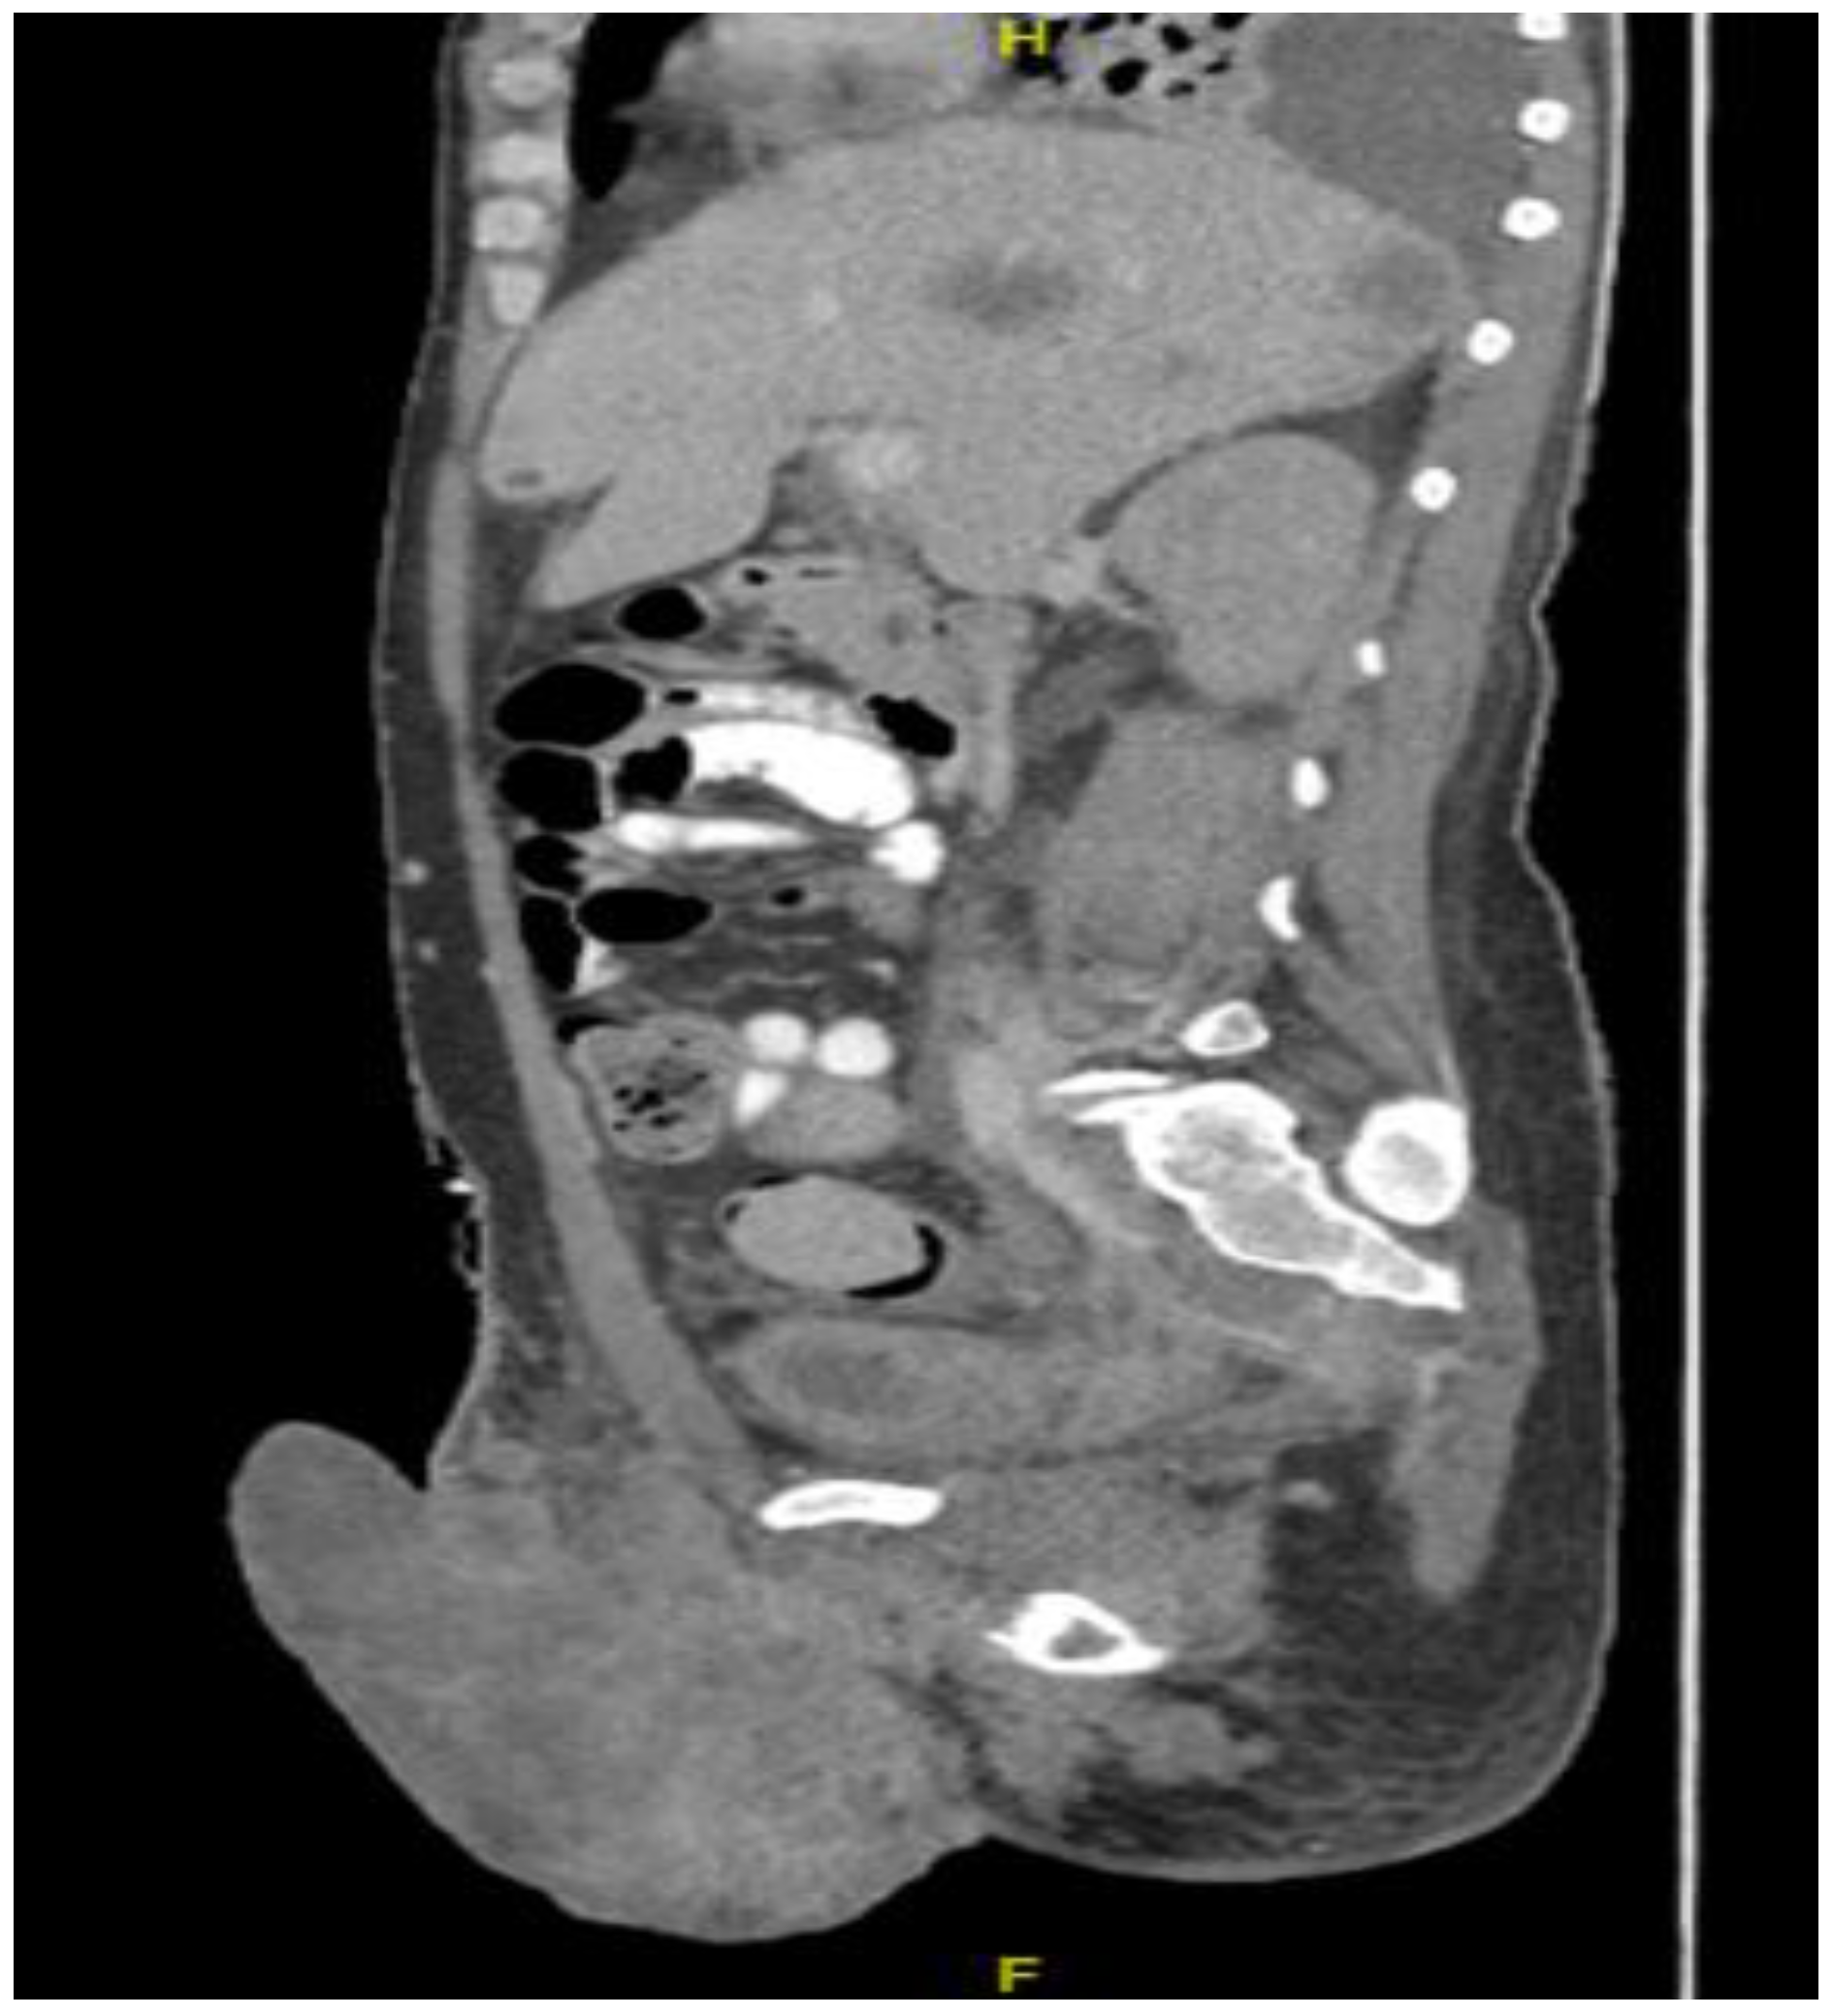

Figure 8.

CT in the sagittal view, abdominal window, showing scrotal mass extending to erect penis.

Figure 9.

CT in the axial view of an abdominal window showing liver metastasis.